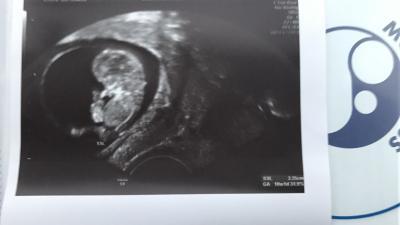

Alles super heute! Baby laut Ärztin auf den Tag genau entwickelt, immer noch "tablettenpackung-Baby", damit meint sie es sieht genauso aus wie auf einer Packung und sehr vorbildlich. Bin ganz stolz Und es hat sich bewegt und gewunken! Es war einfach wunderschön

Bild zu Zurück vom fa :) - Forum für August - Mamis

Glückwunsch! Schönes Foto!

und ein tolles Bild